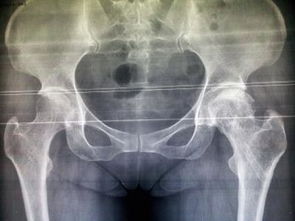

股骨頭壞死即股骨頭缺血性壞死,又稱無菌性股骨頭壞死。其癥狀是由于不同致病原因破壞了股骨頭的血液供應,因骨缺血而發(fā)生股骨頭骨質壞死。 分型:股骨頭壞死的不同類型及壞死范圍和部位對治療方法的選擇起著重要的作用,因此我們結合X片、ECT及手術所見把股骨頭壞死分為以下四型、三級。